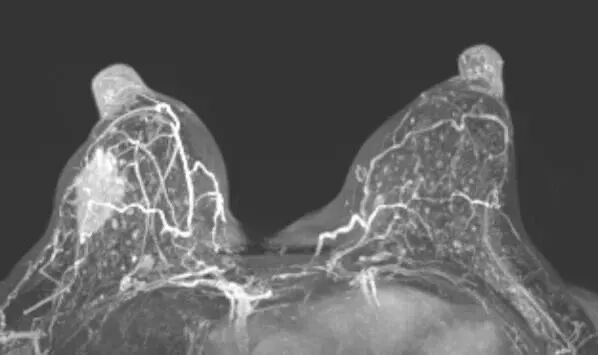

武威重离子中心基于对碳离子放疗特性的深刻理解——精准的剂量分布、强大的生物效应和最小的正常组织损伤,针对现有技术瓶颈进行了系统性创新,实现了三大关键突破:

突破二:个体化精准治疗,安全与疗效的双重保障中心采用自主研发的乳腺专用固定系统(获国家实用新型专利),结合多重固定技术,从源头确保治疗精度。

摒弃传统“一刀切”的剂量模式,根据每位患者的肿瘤特征——包括大小、位置、病理类型等——量身定制治疗方案。通过多角度照射技术,在彻底消除肿瘤的同时,最大程度保护皮肤和正常腺体组织,显著降低并发症风险。